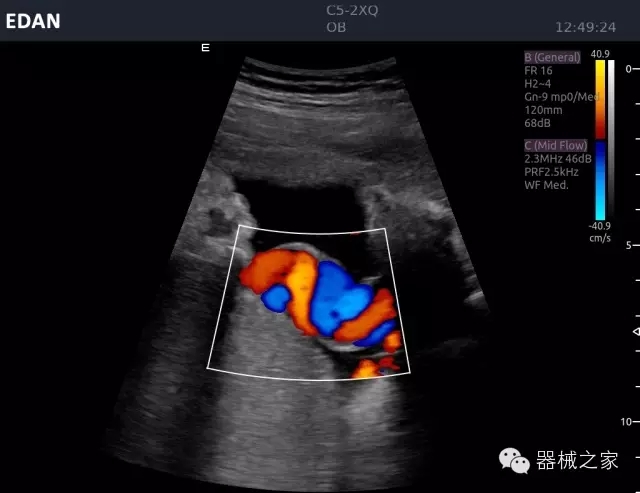

睪丸低速血流

臍帶血流